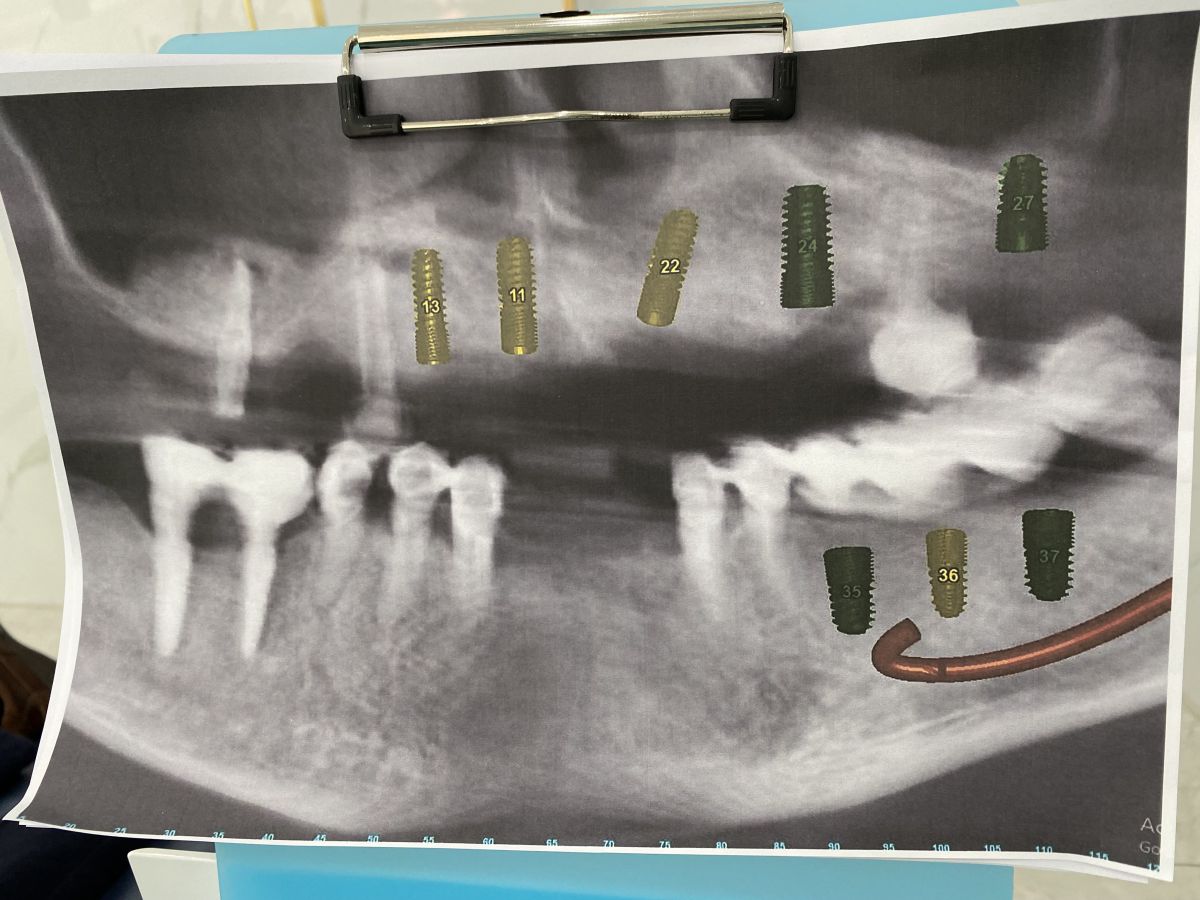

Khi tiếp nhận thăm khám, bác sĩ nhận thấy:

- Hàm trên: chỉ còn lại vài trụ Implant cũ đã được đặt cách đây hơn 10 năm, hiện nay có dấu hiệu tiêu xương quanh trụ, không còn đảm bảo chức năng nâng đỡ phục hình.

- Hàm dưới: nhiều mão sứ và cầu răng đã xuống cấp, lỏng, gãy, gây mất cân đối khớp cắn và ảnh hưởng đến khả năng ăn nhai.

- Xương hàm có dấu hiệu tiêu và mỏng, cần được đánh giá kỹ qua phim CT ConeBeam 3D để xác định có cần ghép xương, nâng xoang trước khi cắm trụ mới.